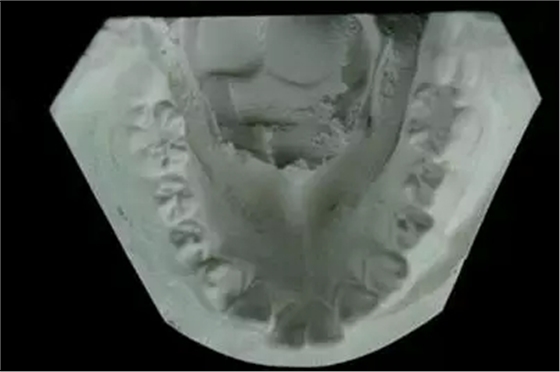

(2) 評(píng)估和記錄牙體解剖形態(tài)

(3) 評(píng)估和記錄牙弓形態(tài)

(5) 評(píng)估和記錄<牙合>曲線(xiàn)

(8) 檢查牙<牙合>異常情況